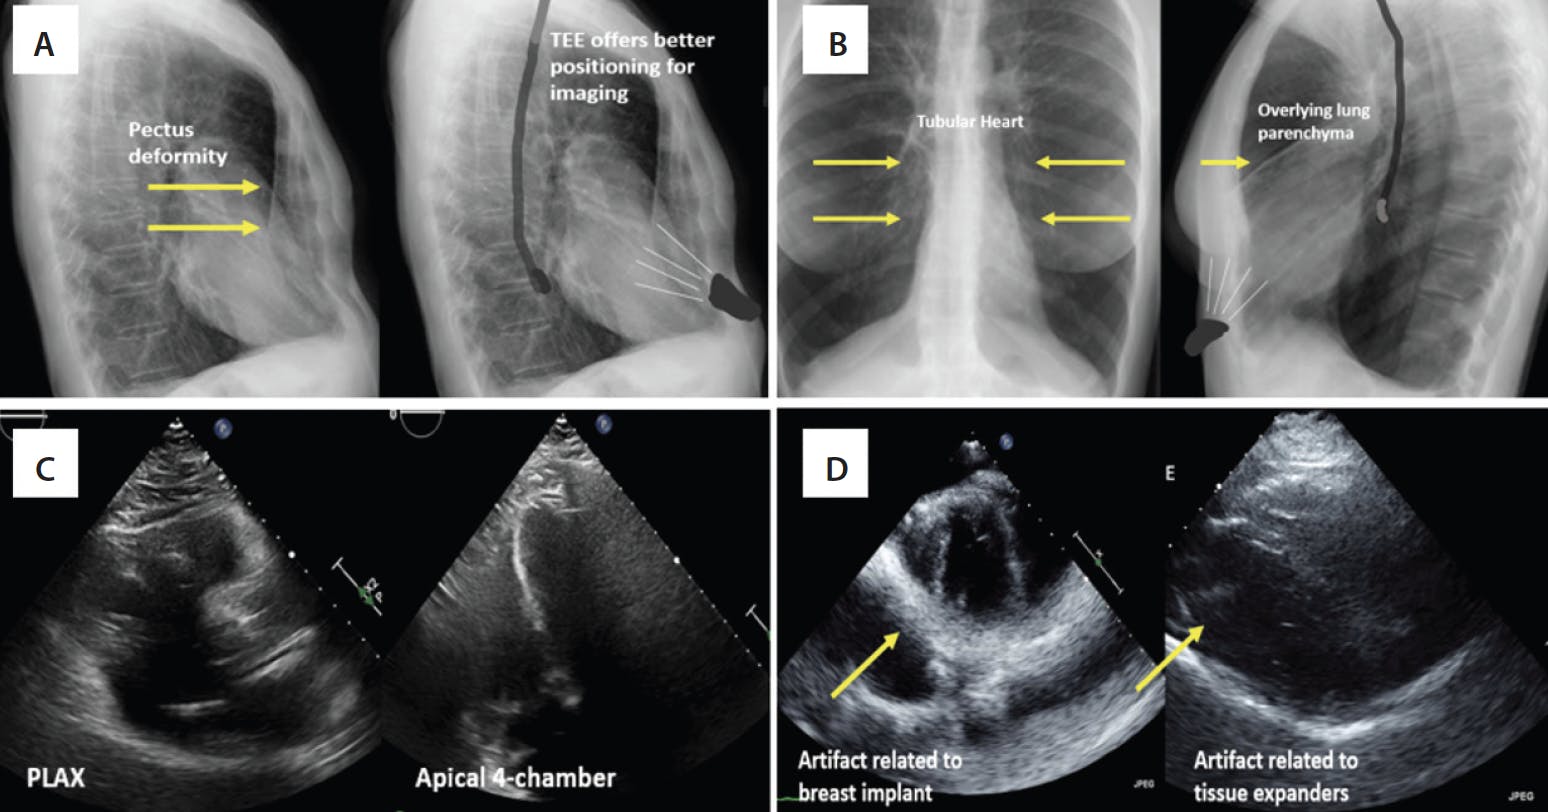

Transthoracic imaging is routinely used for the majority of uncomplicated TAVR procedures. However, occasionally TTE imaging falls short in providing adequate assistance during intraprocedural imaging. TEE has greater spatial resolution when compared to TTE. It can override the common challenges faced by TTE during intraprocedural imaging, such as supine imaging instead of left lateral, barrel-shaped chest due to emphysematous lungs in chronic obstructive pulmonary disease, radiation-related AS in patients with breast implants, and TAVR in patients with chest wall deformities like pectus excavatum. Factors that might urge providers to consider upfront TEE instead of the routinely performed TTE are described in Table 1.

Furthermore, important preassessment details such as presence of AR, other coexisting valvular pathology, intracardiac thrombus or significant aortic atheroma can be overlooked with poor TTE imaging windows. One of the most important markers of procedural success is the absence of paravalvular leak (PVL). Suboptimal imaging windows may preclude assessment of PVL and may underestimate the degree of paravalvular regurgitation. More than mild (1+) PVL is directly related to poor outcomes, according to multiple prospective studies.7-9 The accurate location and degree of PVL cannot be assessed with certainty with an aortogram under fluoroscopy alone. Figure 1 shows the various examples of challenges faced with TTE imaging in certain patient populations.

Figure 1. Chest x-ray of a patient with a pectus deformity showing the sternal distortion. The position of TTE and TEE is shown in relation to the heart (A). Chest x-ray and relative positioning of probes in a patient with chronic obstructive pulmonary disease and a tubular heart and overinflated lungs (B). Suboptimal parasternal long axis (PLAX) and apical four-chamber imaging windows in a patient undergoing TAVR (C). Patient with breast implants showing significant artifact preventing visualization of aortic valve (D).